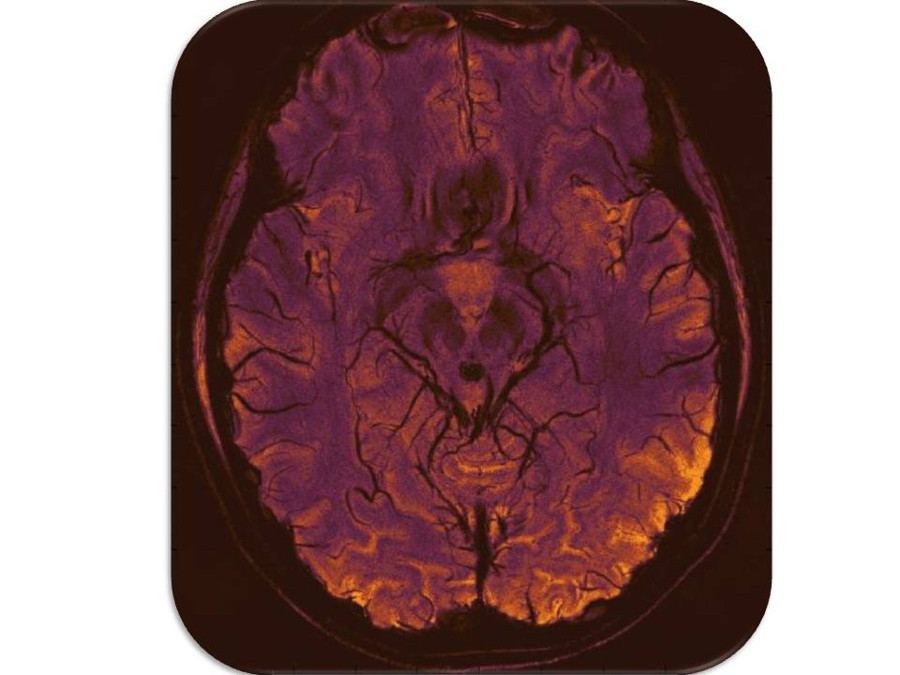

(11) Black Widow _small